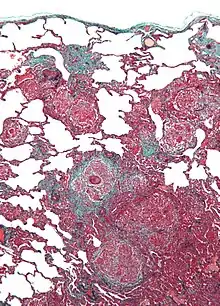

| Micrograph of hypersensitivity pneumonitis, the histologic correlate of bird fancier's lung. Lung biopsy. Trichrome stain. | |

Bird fancier's lung (BFL), also known as bird breeder's lung, is a type of hypersensitivity pneumonitis. It can cause shortness of breath, fever, dry cough, chest pain, anorexia and weight loss, fatigue, and progressive pulmonary fibrosis (the most serious complication). It is triggered by exposure to avian proteins present in the dry dust of droppings or feathers of a variety of birds. The lungs become inflamed, with granuloma formation. It mostly affects people who work with birds or own many birds.

BFL causes inflammation of the alveoli in the lungs. Avian proteins include mucins and antibodies, which stimulate a significant immune response from the body.[3] The lungs become inflamed, with granuloma formation. It can take many years of exposure to cause BFL, with an average of 1.6 years to cause acute disease, and 16 years to cause chronic disease.[2]

Lung biopsy usually reveals non-necrotizing granulomatous inflammation.[7] It also shows "foamy" macrophages and crystals of oxalic acid.[3] Hyperplasia tends to occur in type 1 pneumocytes and not in type 2 pneumocytes.[3]